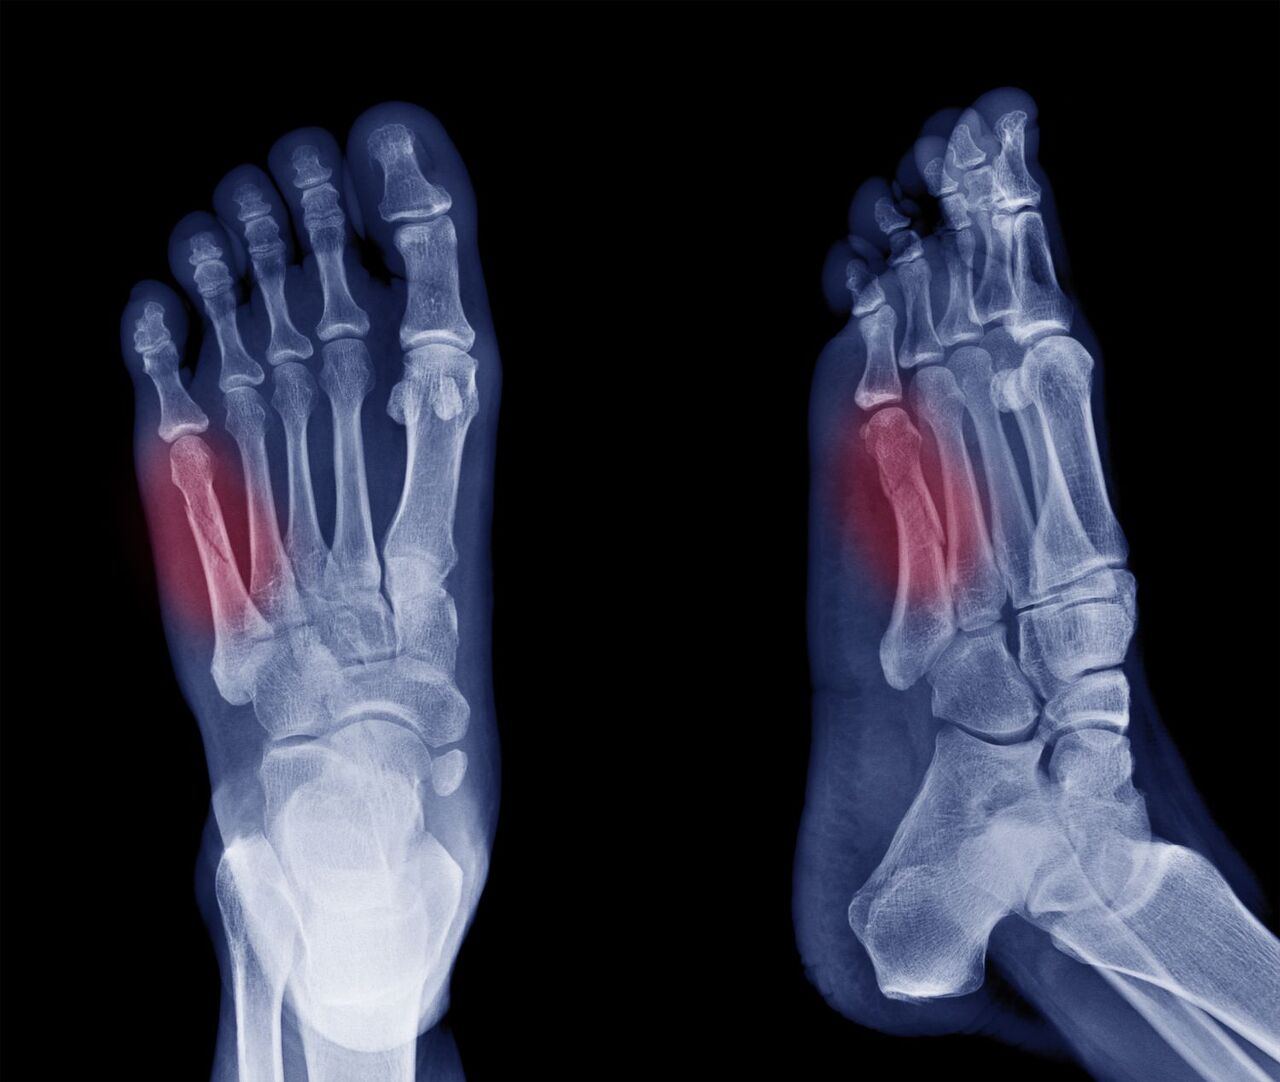

발가락 골절은 흔히 발생하는 상황입니다. 이유는 다양하게 있을 수 있으며, 대표적으로는 실내에서 물건에 부딪히거나 높은 곳에서 떨어지는 등의 사고가 있습니다. 이 외에도 스포츠 활동 중 부상을 당하거나 교통사고 등에서도 발가락 골절이 발생할 수 있습니다. 발가락 골절은 크게 뼈가 완전히 부러진 경우와 뼈에 금만 간 경우로 나눌 수 있으며, 이에 따라 치료 방법과 기간이 다릅니다.

- 깁스 치료: 뼈가 크게 부러진 경우에는 깁스로 고정하는 방법이 일반적입니다.

- 스플린트: 뼈에 금만 간 경우, 즉 미세한 골절의 경우에는 발가락용 스플린트로 치료가 가능합니다.

- 수술: 복합 골절이나 압박 골절의 경우에는 핀을 박는 수술이 필요할 수 있습니다.

- 금속판 사용: 뼈가 조각나거나 비스듬하게 부러진 경우에는 금속판을 덧대어 고정하기도 합니다.